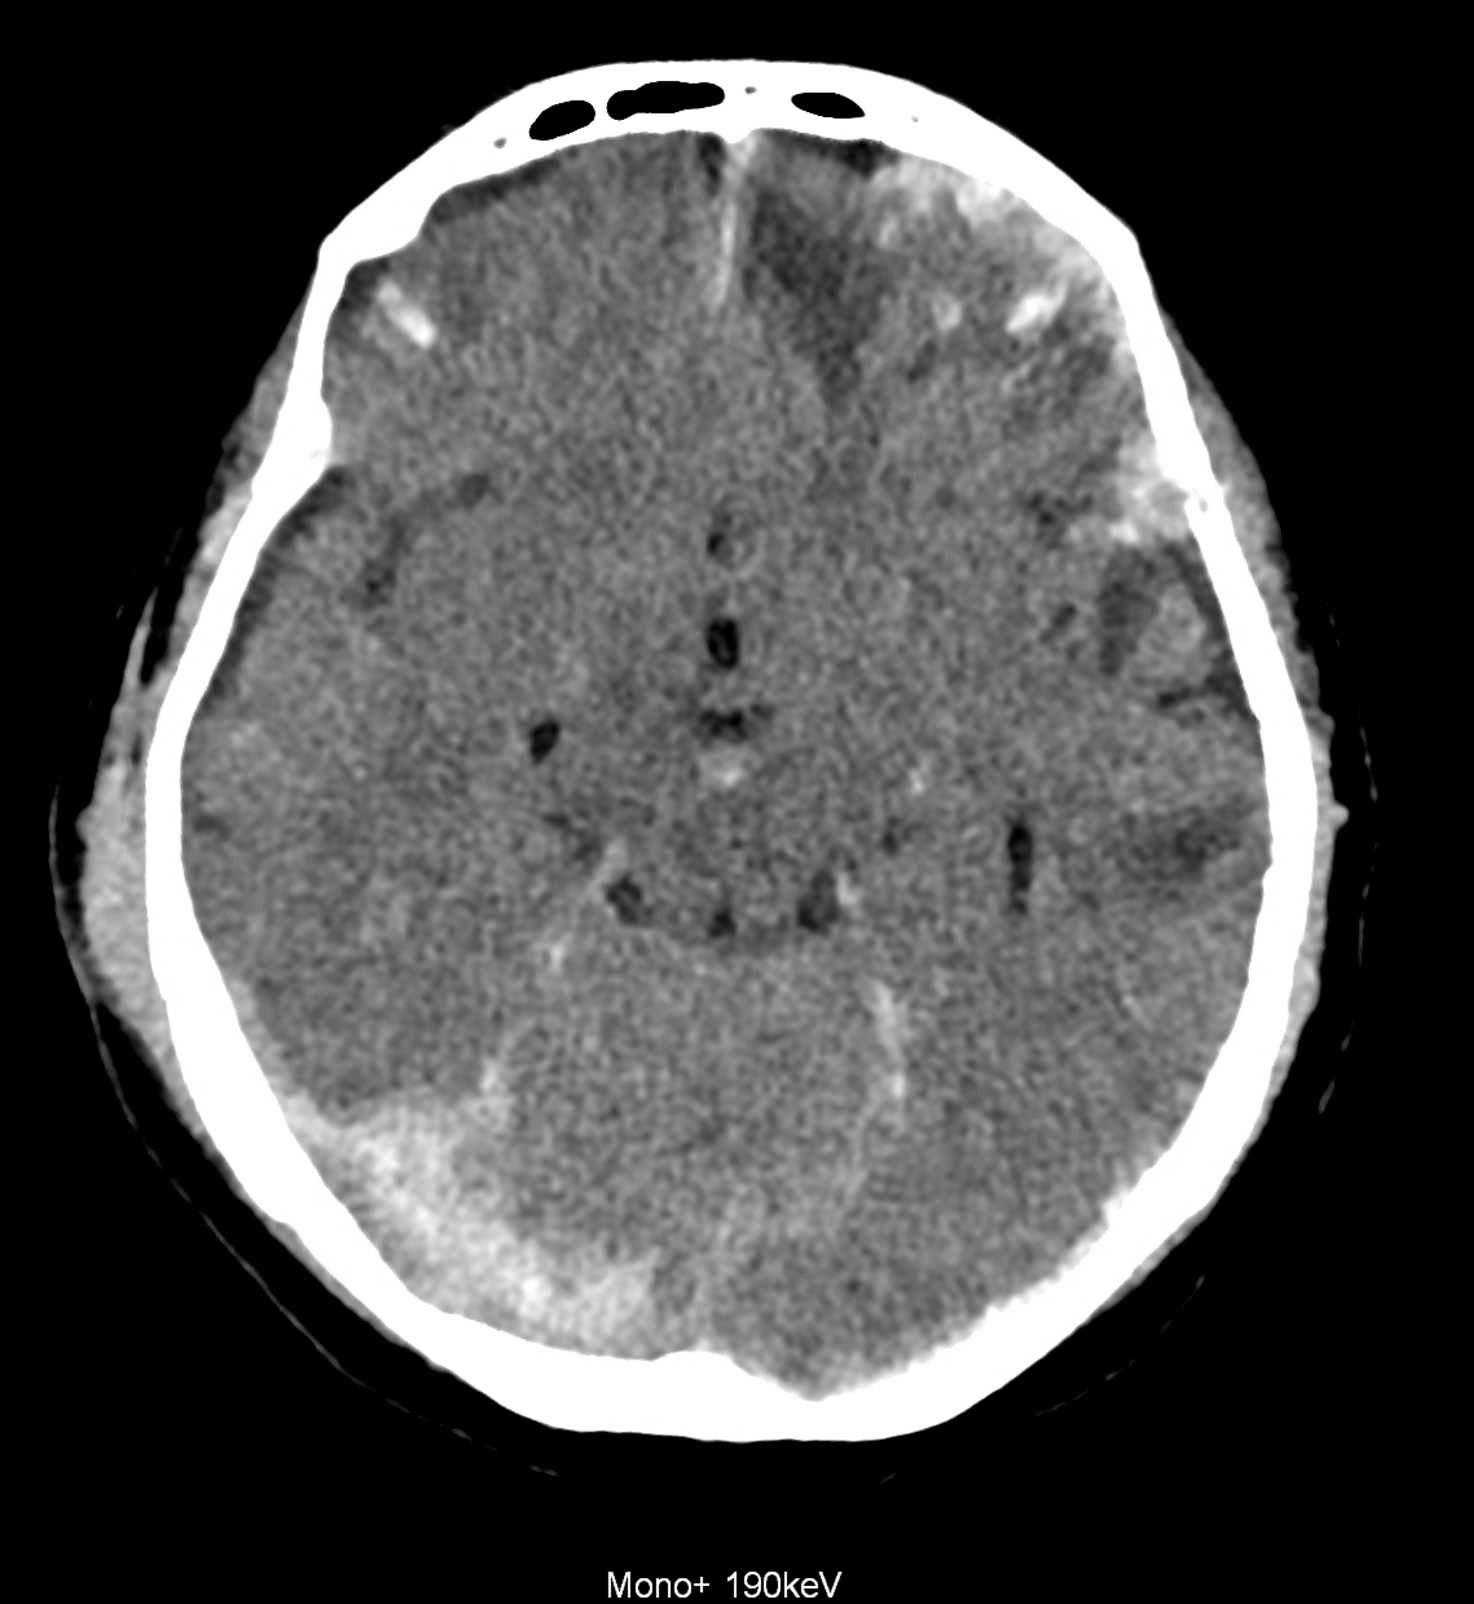

Bleeding is characterized by different absorption characteristics than healthy brain tissue (both gray and white matter) and cerebrospinal fluid. Due to the higher proportion of proteins with amino acids with disulfide bonds, the signal intensity increases at higher energies, making it possible to use monoenergetic imaging at energies above 140 keV, and/or virtual non-contrast. The hemorrhage then becomes more hyperdense, while the rest of the brain tissue acquires a uniform low signal. In addition to bleeding, areas of extracellular fluid of vasogenic origin are also imaged, i.e., in areas around contusion-type brain tissue injuries.

An example of the use of spectral imaging in complex brain injury, where contusions, diffuse axonal injury, subarachnoid hemorrhage, subdural hemorrhage, and blood in the ventricular system are present.

comparison of the images with the energies of monoenergetic reconstructions 40 keV, 67 keV (standard conventional reconstruction), 190 keV and virtual non contrast (VNC)